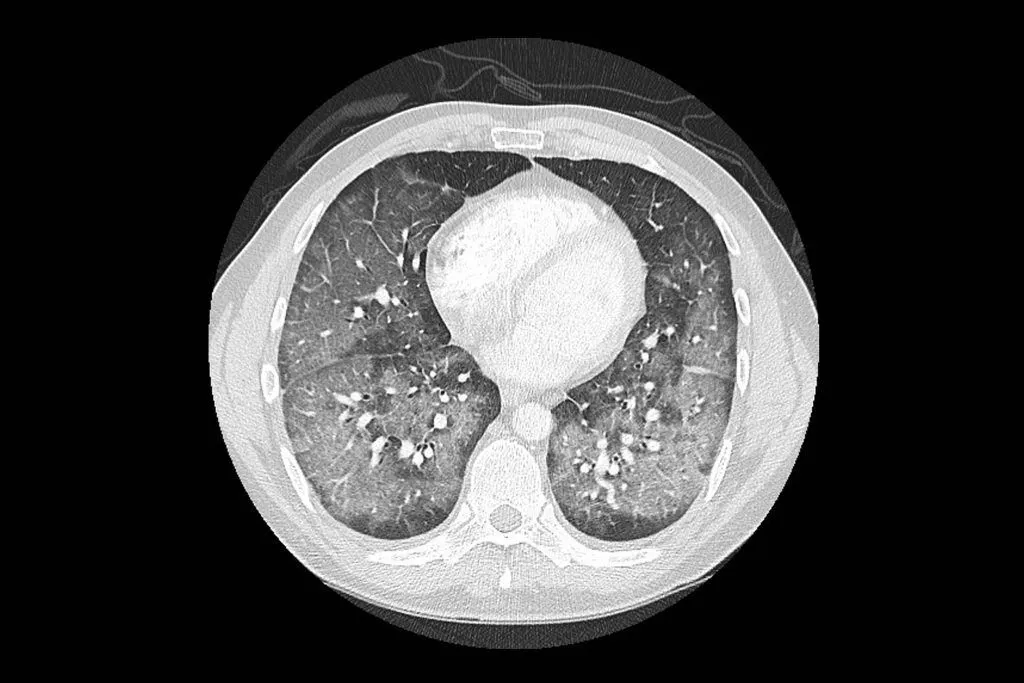

Fuente: Radiografía y scanner de pacientes con daño asociado al consumo de cigarrillo electrónico The New York times

Los casos se han presentado con aparición gradual de síntomas y siempre con el antecedente de haber usado cigarrillos electrónicos, ya sea con nicotina o con THC (constituyente del cannabis) (2). De estos últimos, se ha identificado que la mayoría contenía vitamina E acetato. Los síntomas reportados son: dificultad respiratoria y dolor en el pecho. Algunas personas también han informado padecer síntomas gastrointestinales, como vómitos y diarrea. También han registrado otros síntomas como fiebre, taquicardia y fatiga.

Este síndrome respiratorio se ha dado en un contexto no infeccioso, por lo que los especialistas están investigando cuál es el rol de los cigarrillos electrónicos en los casos.